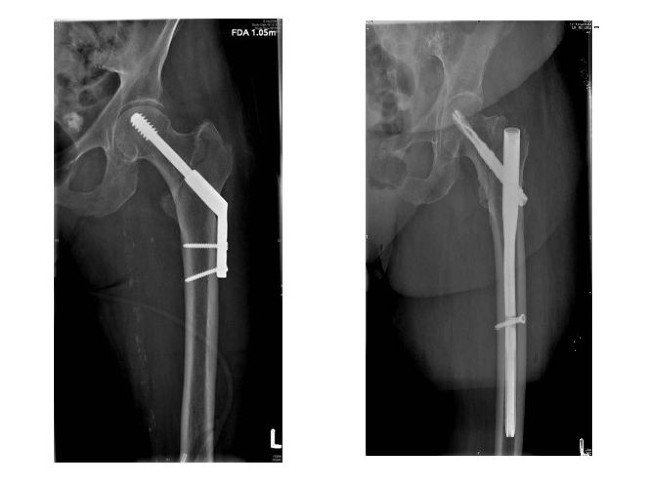

Gute Lösungen für stabile Frakturen sind Platte-Schrauben-Kombinationen (DHS) und für instablie Frakturen die sogenannten cephalo-medullären Nagel (Gamma- oder Proximaler Femurnagel)